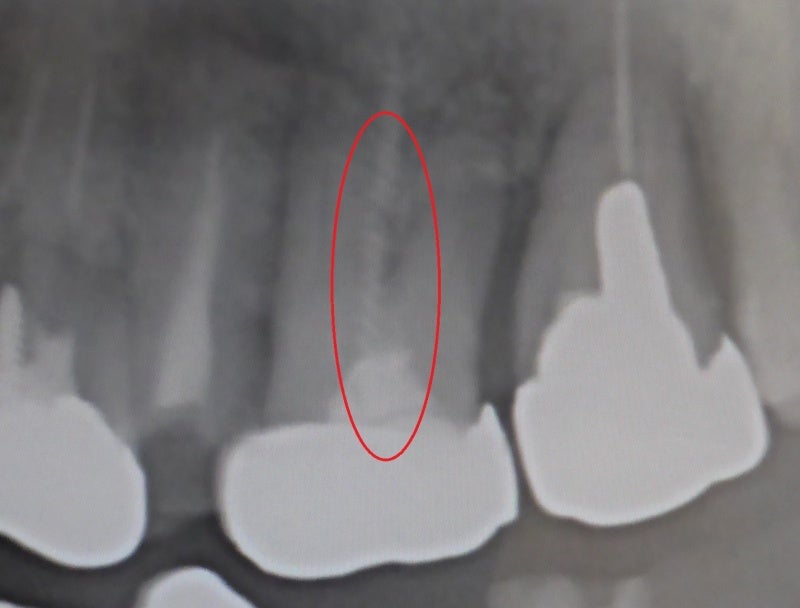

当院で 5年ほど前に入れた入れ歯です。

入れ歯が折れたと 久しぶりに来院にされました。

気に入っていた入れ歯を

作りなおさないといけないか心配していました。

修理可能です!!

預かって 技工所で 修理します。

きれいに修理できました。

どんな入れ歯も修理できるわけではありませんが、